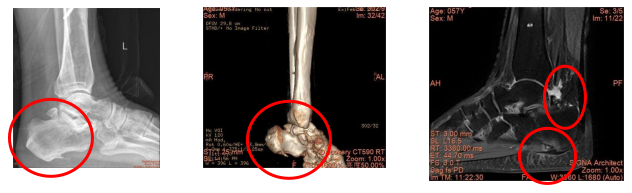

57歲的陳先生因左踝關節后側疼痛半年,且疼痛程度逐漸加重,現影響行走,就診于我院手足外科。經檢查,陳先生有左踝關節撞擊綜合征、左距后三角骨、左跖筋膜炎、左跟骨骨刺、左距骨軟骨損傷等多種病癥。

術前檢查發現后踝三角骨撞擊,跖筋膜炎

這種微創新技術通過在踝關節鏡后入路打兩個0.5cm的小孔,在關節鏡下切除距后三角骨;同時,最大限度減小足跟處切口,使用關節鏡切除部分跖筋膜,用刨刀切除骨刺,完成跖筋膜炎松解和骨刺治療,最大化實現手術治療效果。目前,陳先生后踝、足跟疼痛消失,等待傷口愈合。